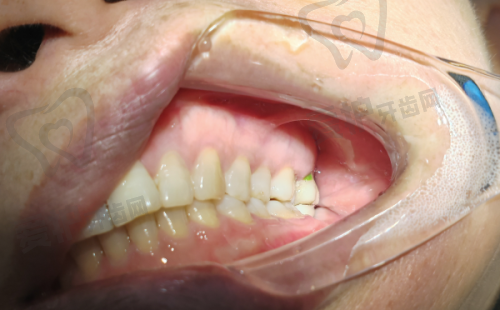

为了让大家更好地了解重庆团圆口腔医院李志锋医生开展的以色列种植牙项目,下面为大家分享一个患者实例。张先生是一位50多岁的患者,由于长期的牙齿缺失,导致咀嚼功能下降,面部也出现了一定程度的凹陷。他在朋友的推荐下来到了重庆团圆口腔医院。

李志锋医生为张先生进行了详细的检查后,建议他进行以色列种植牙手术。在与张先生充分沟通后,制定了适合他的种植方案。手术过程非常顺利,张先生在术后修复得也特别快。现在,张先生已经成功戴上了种植牙,他的咀嚼功能得到了明显改善,面部也修复了饱满。张先生对种植成效非常满意,他说:“没想到种植牙能让我的生活发生这么大的改变,感谢重庆团圆口腔医院和李志锋医生。”